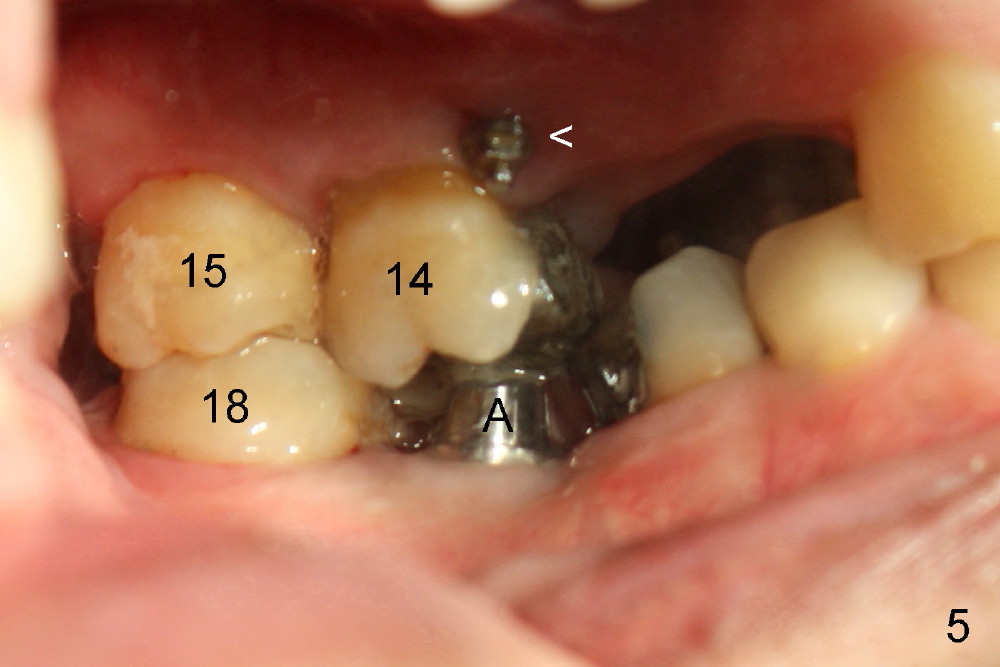

Mr. Zhou is in his fifties. Finally he starts implant restoration. But he has financial constraint. It appears that implant restoration at the site of #19 is the most rewarding in term of restoration of his mastication with a single implant (Fig.1). The implant is apparently placed at the proper level (Fig. 2: I, 6x17 mm). The implant is osteointegrated with minimal bone resorption at crest six months later (Fig.3). The teeth #15 and 18 cannot occlude when 4.5x5 mm abutment (Fig.4: A) is placed at #19 implant (<). It takes a while to trim the unipost from the top gradually in order to let #15 and 18 have normal occlusal contact (Fig.5 mirror image). By that time, the abutment is approximately 2.5 mm tall.